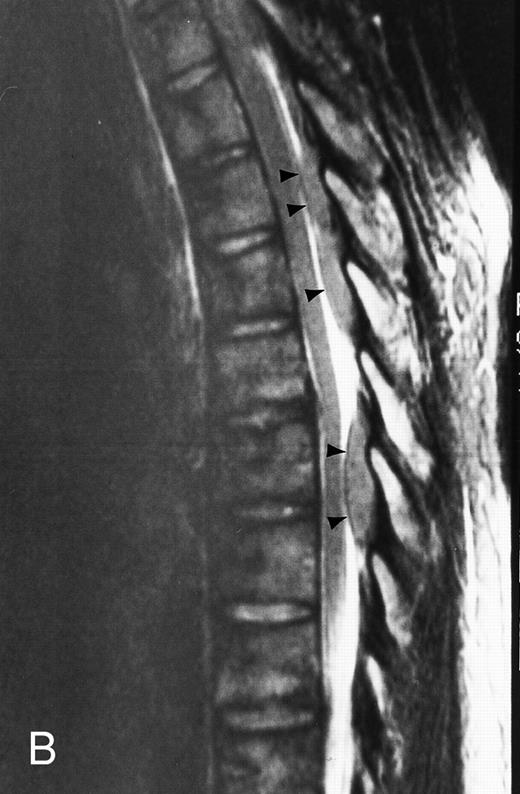

Normal appearance of spinal bone marrow in a 45-year-old woman: T1-weighted (500/11, TR/TE) (A) and T2-weighted, fat-suppressed fast spin echo (4000/96, TR/TE, ET 16) (B) sagittal MR images of the lumbar spine. Note increased signal of the vertebral bodies, relative to the intervertebral discs in (A) and increased deposition of fatty marrow around the basivertebral veins (arrowheads). On the T2-weighted image, normal intervertebral discs are brighter than the vertebral bodies; low signal in the L4-L5 and L5-S1 discs is due to degenerative changes (arrows).